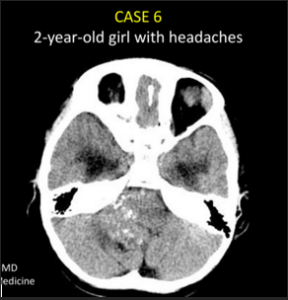

A 3-year-old child is admitted to the hospital due to decreased appetite and weight loss. She has been afebrile, and has not had vomiting or diarrhea.

Her activity level has decreased over the past two weeks.